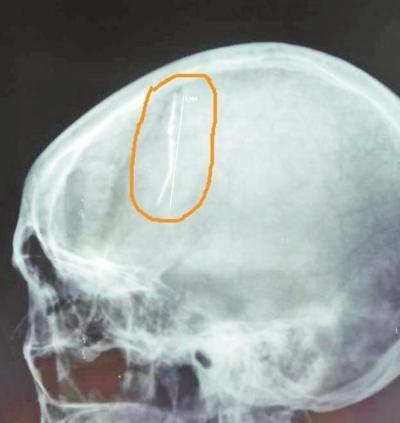

随后,王晓红被家人送往大医院检查。据医院神经外科副主任介绍,王晓红入院后,医生为其做了头颅X线检查。令人不可思议的是,检查结果显示,在她的脑部竟然有一根六七厘米长的钢针,从病人的右侧大脑顶部直插入左侧大脑深部。

针已生锈估计已有几十年

在病因被确诊之后,医护人员抓紧制订治疗方案,希望可以尽快将异物安全取出。医生们决定为其实施开颅手术。在手术过程中,医生发现这根针已经生锈,被新生粘连的组织血管包裹住了,不能一下子拔出,且钢针已经深入对侧脑室内,如果贸然拔出可能会导致不可预料的大出血。

这无疑增大了手术的难度。在显微镜下,医生小心翼翼地将一根根新生血管及粘连的脑组织剥离,切开两侧大脑半球间的大脑镰,经过两个多小时的“雕刻式切除”,终于将藏于王女士大脑内的钢针完整地取出。目前,病人已顺利出院。